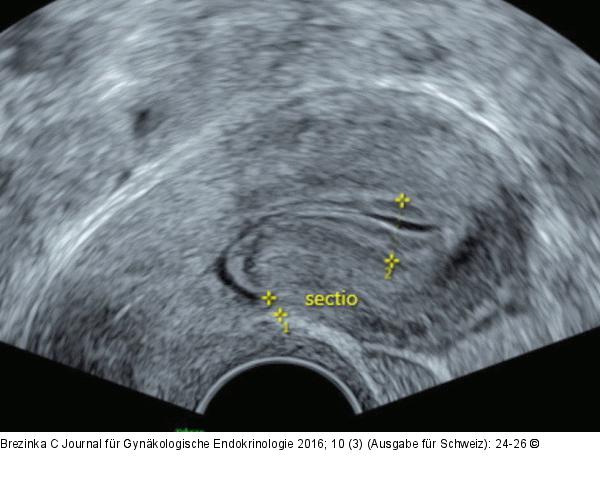

Abbildung 8: Ultraschall-Serometra Markante Sectionarbe am nichtschwangeren Uterus am 10. Zyklustag, Darstellung mit NaCl. Die residuale myometriale Dicke (RMT) beträgt 3 mm. |

Markante Sectionarbe am nichtschwangeren Uterus am 10. Zyklustag, Darstellung mit NaCl. Die residuale myometriale Dicke (RMT) beträgt 3 mm. |